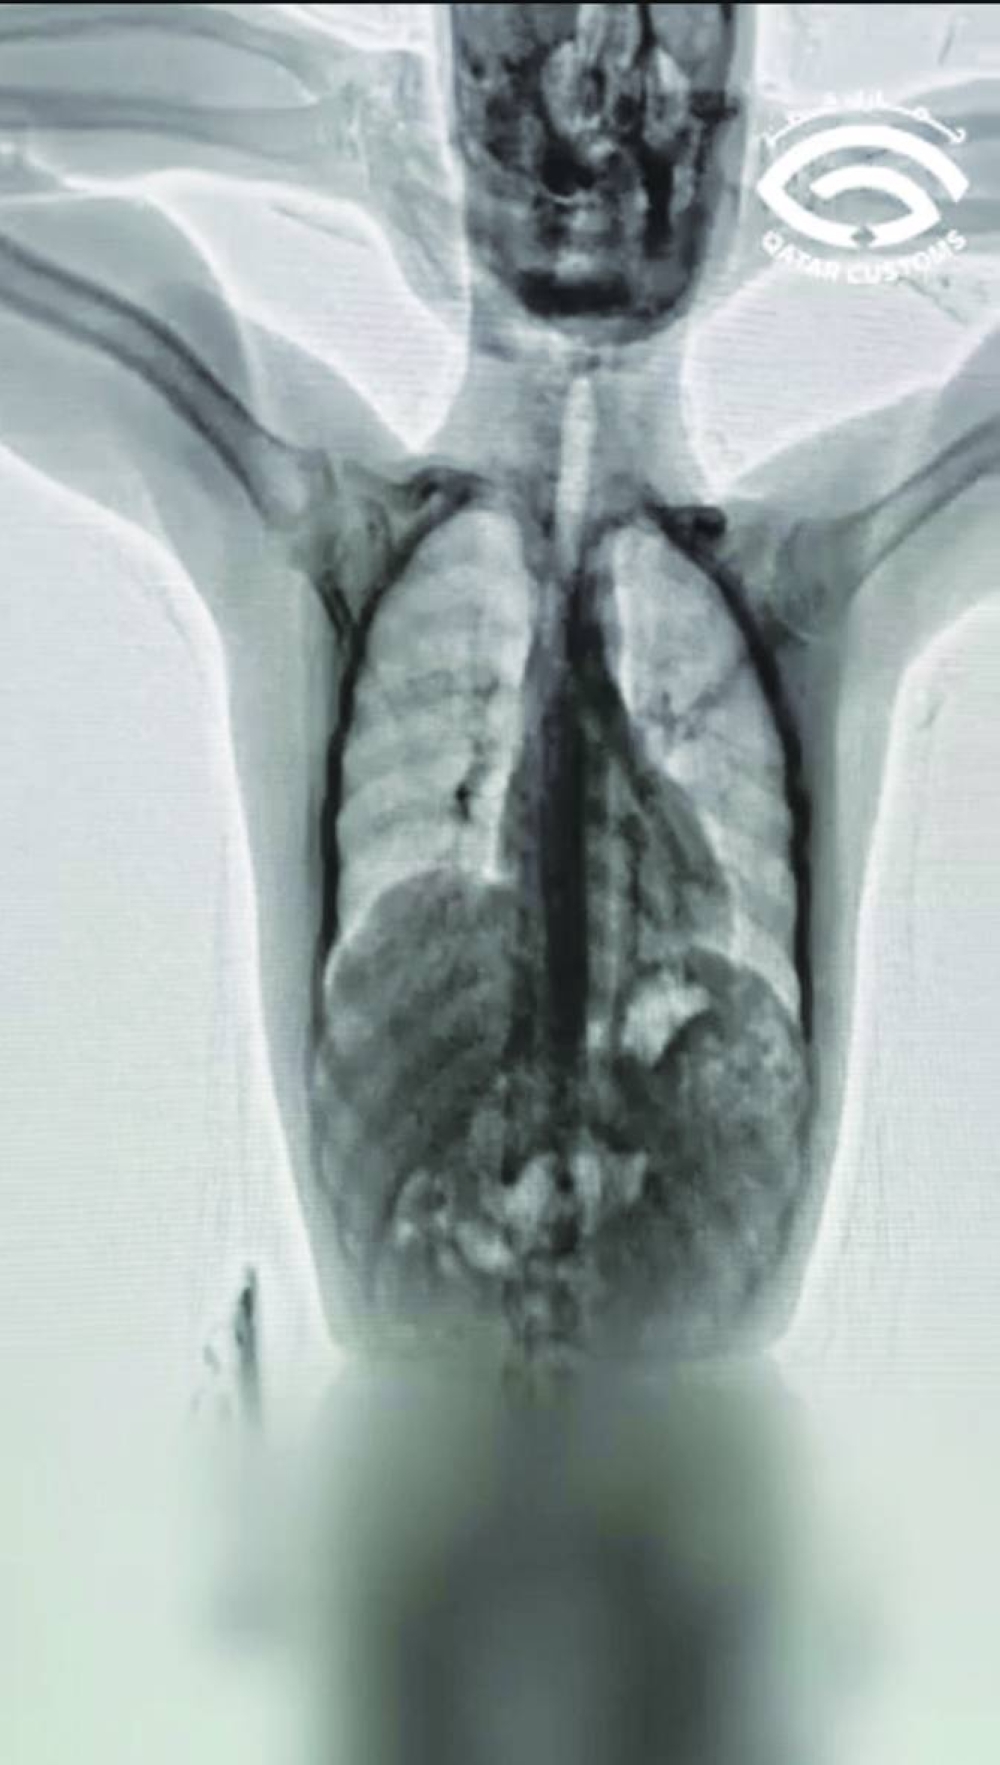

According to a statement by the General Authority of Customs (GAC) on X, shabu and heroin were seized from a passenger at the airport. The narcotic substances were found after the passenger underwent a check by the officials on suspicion. When the passenger underwent body scanning, narcotic substances were found inside the stomach.

As much as 80 capsules, weighing 610g, were recovered from his stomach.